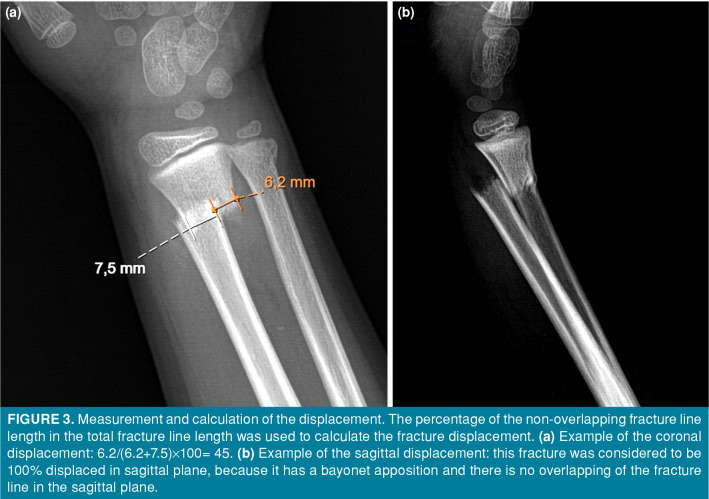

The evaluations and measurements were performed using the Sectra version 22.1 software (Sectra AB, Linköping, Sweden). Since the risk of alignment changes after the fourth week in this age group is very low, the fourth week was chosen as the endpoint for radiological measurements.[7] At the time of admission, immediately after the reduction, the first-week, second-week, and fourth-week controls were analyzed. The types of fractures were recorded. Sagittal and coronal plane angulations and translation percentages of the radius at each visit were calculated (Figures 2 and 3). The Δcoronal angle, Δsagittal angle, Δsagittal translation and Δcoronal translation values were calculated by subtracting the measurements after reduction from the measurements at the fourth week of the cases. During follow-up period, cases that required re-reduction or surgical intervention by exceeding the acceptable reduction criteria were accepted as unsuccessful treatments.

Figure 3. Measurement and calculation of the displacement. The percentage of the non-overlapping fracture line length in the total fracture line length was used to calculate the fracture displacement. (a) Example of the coronal displacement: 6.2/(6.2+7.5)x100= 45. (b) Example of the sagittal displacement: this fracture was considered to be 100% displaced in sagittal plane, because it has a bayonet apposition and there is no overlapping of the fracture line in the sagittal plane.